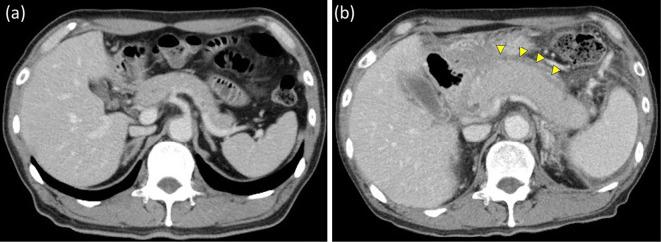

Erdheim-Chester Disease with Pancreatic Enlargement Observed Using Contrast-enhanced Endoscopic Ultrasonography.

We herein report an unusual case of Erdheim-Chester disease (ECD), a rare non-Langerhans cell histiocytosis, and emphasize its unique presentation and diagnostic challenges. Our patient exhibited uncommon symptoms and significant organ involvement, particularly pancreatic enlargement that is not typically associated with ECD. Contrast-enhanced harmonic endoscopic ultrasonography (CEH-EUS) and EUS-fine needle aspiration (EUS-FNA) play crucial roles in the comprehensive assessment of the disease, demonstrating their superiority in identifying and characterizing elusive ECD lesions. This is the first report to document pancreatic lesions in patients with ECD evaluated using CEH-EUS. EUS-FNA is valuable for diagnosing rare diseases, including ECD, with diffuse pancreatic enlargement.